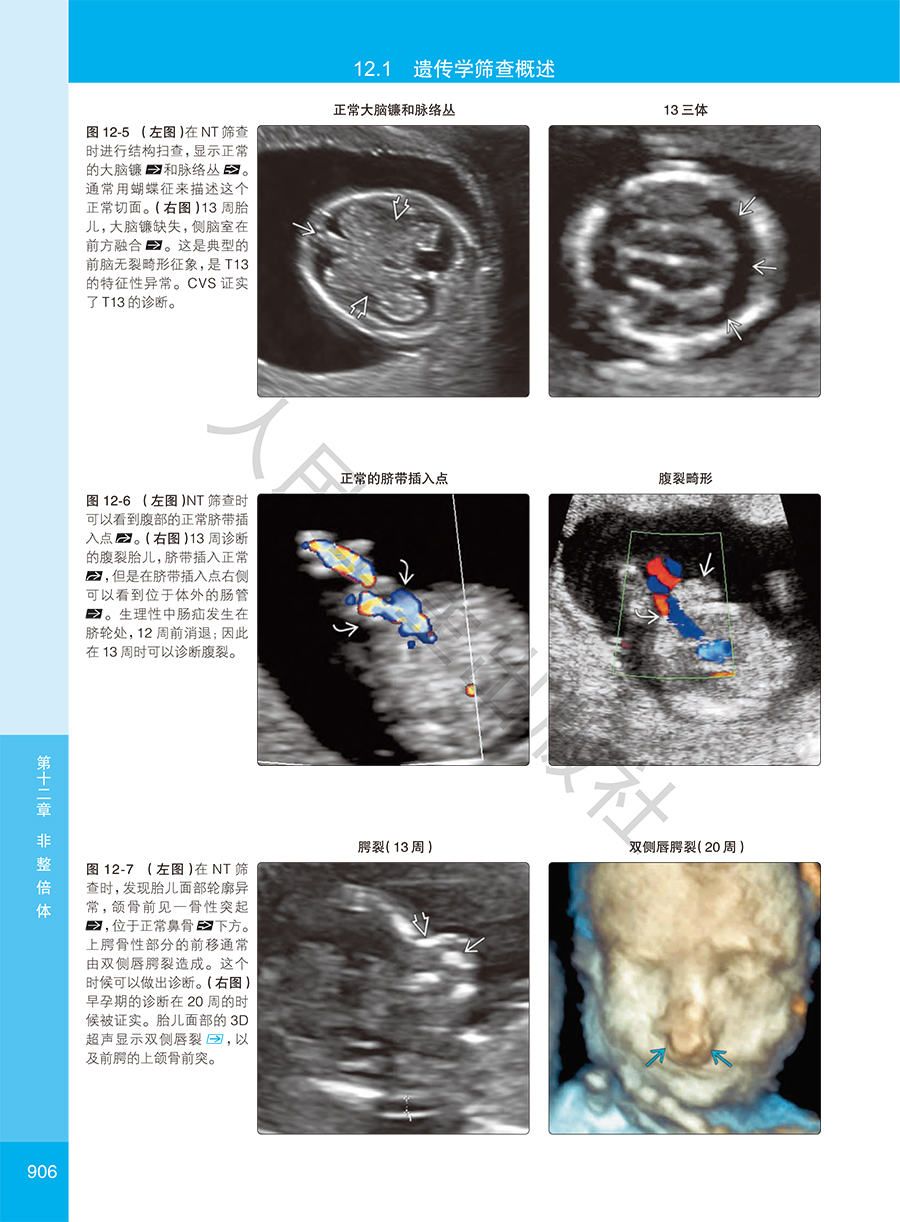

本书是美国妇产学会针对产科影像诊断从业人员专业提升编写的围生期诊断与筛查高级参考图库,专科医师培训的优秀教材。全书共16章314节,用5000多幅精美照片详细图解了胎儿大脑、脊柱、面部和颈部、胸、心脏、腹壁、胃肠道、泌尿生殖系统、肌肉骨骼、脐带、胎盘和胎膜在孕早、中、晚期的正常与常见异常情况的经典影像特征和相关鉴别论断,并对多胎妊娠、染色体异常、综合征和多系统疾病、感染性疾病等特殊状况的早期诊断进行了经验独到的讲解,对孕期母体相关疾病的影像论断与鉴别也进行了专门论述。